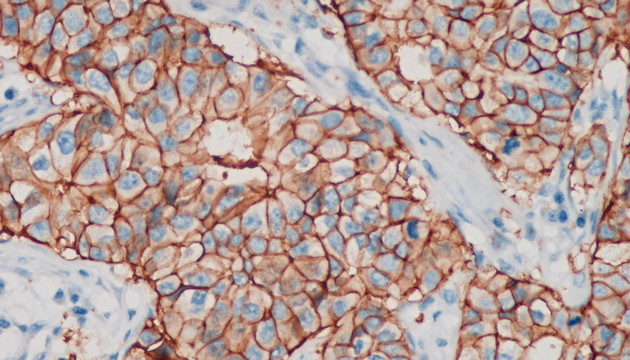

依據(jù)癌細胞在分子表達層面和細胞組織層面的變化,運用各類顯微成像技術對癌細胞進行篩選與識別,如①病理切片②免疫組化(IHC)③原位熒光雜交(FISH)④循環(huán)腫瘤檢測(CTC)⑤腫瘤細胞培養(yǎng)研究

(1)全能型設備:明美數(shù)字切片掃描系統(tǒng)MDS4+MSX2/MS60,融合切片掃描功能與研究級熒光顯微鏡,適用于病理切片、CTC、FISH、IHC等多種檢測。 (2)FISH、CTC、IHC專用:MF43-N/MF53-N+MS23/MSX11,搭配FISH軟件,支持多色熒光通道,高靈敏度成像,智能優(yōu)化圖像。 (3)癌細胞培養(yǎng)觀測:活細胞成像儀MCS11/MCS21/MCS22+電腦,培養(yǎng)箱內使用,無線連接遠程管理,減少污染風險,集成多種成像模式,滿足多樣細胞培養(yǎng)觀測需求。